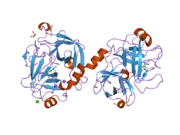

Kallikrein-related peptidase 4 is a protein which in humans is encoded by the KLK4 gene.[5][6][7]

Kallikreins are a subgroup of serine proteases having diverse physiological functions.[8] Growing evidence suggests that many kallikreins are implicated in carcinogenesis and some have potential as novel cancer and other disease biomarkers. In particular, they may serve as biomarkers for both prostate cancer and breast cancer.